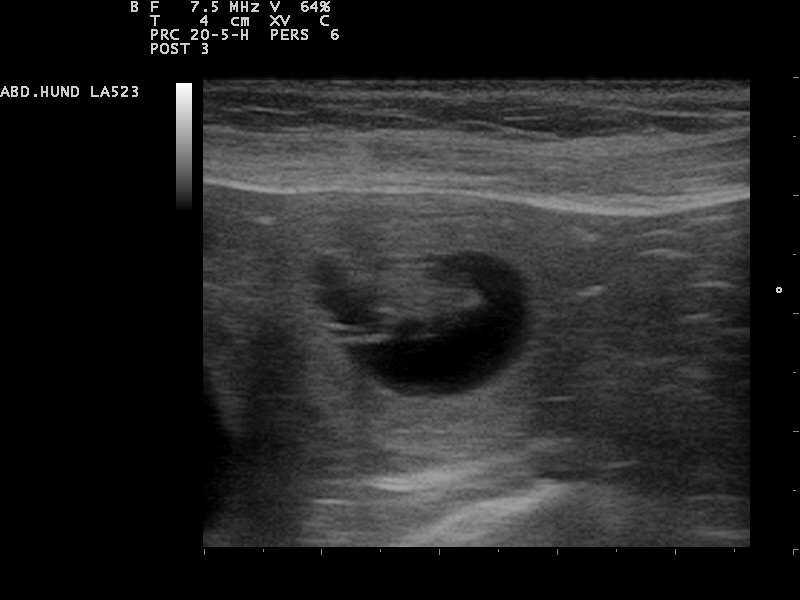

Am 22. Tag sind die Embryonen sichtbar. Der Herzschlag kann zur Diagnose der Trächtigkeit herangezogen werden. Anstrengende Aktivitäten sind

15.12.2015 jetzt zu vermeiden.Die Proteinzufuhr im Futter kann erhöht werden. Hierfür eignet sich sehr gut die Gabe von Welpenfutter. Zu diesem Zeitpunkt kann

mit einer Ultraschalluntersuchung der Zustand der Trächtigkeit festgestellt werden. Besprechen Sie mögliche Risiken einer solchen Untersuchung mit dem Tierarzt.

22.12.2015 Dies ist der beste Zeitpunkt, um die Trächtigkeit anhand des Herzschlags zu diagnostizieren.

Die Embroynen sind etwas walnussgroß und sind gleichmäßig im Uterus verteilt.

Die Ultraschall-Untersuchung hat ergeben das Alexa trächtig ist und wir gespannt auf

unseren B-Wurf warten können

Das sind die ersten Bilder unseres B-Wurfes